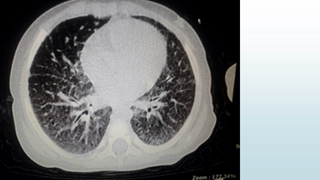

تشخيص :

Pulmonary Alveolar Microlithiasis